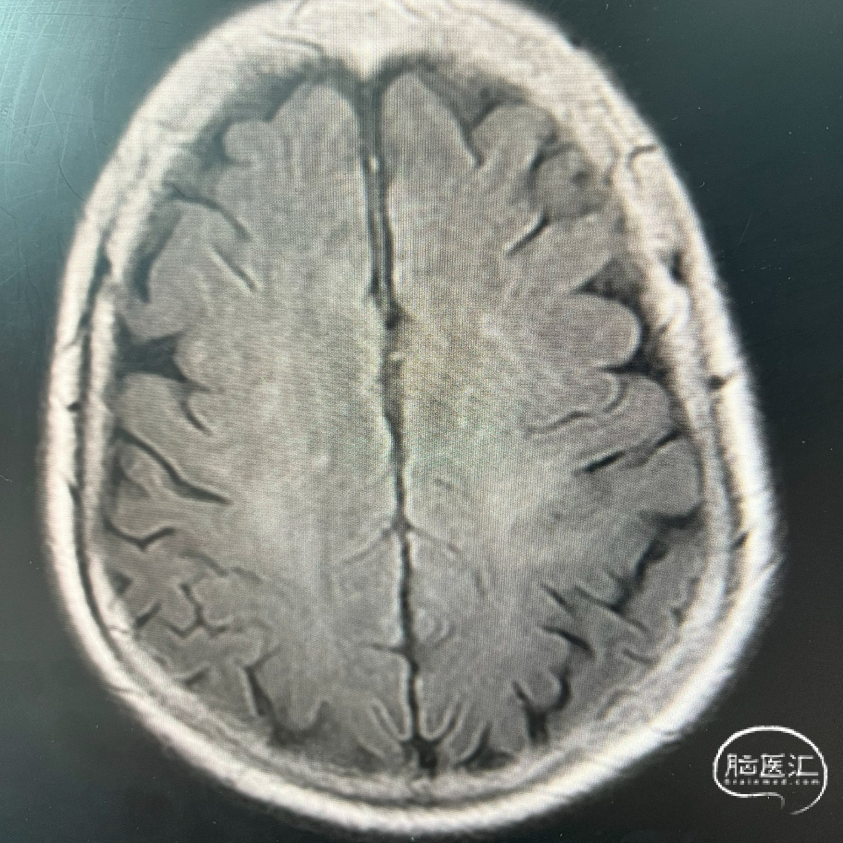

术前FLAIR

术前DWI

影像学表现: